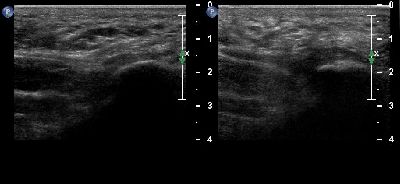

Tendinopatia del muscolo peroneo lungo (2) tendine del m. peroneo lungo